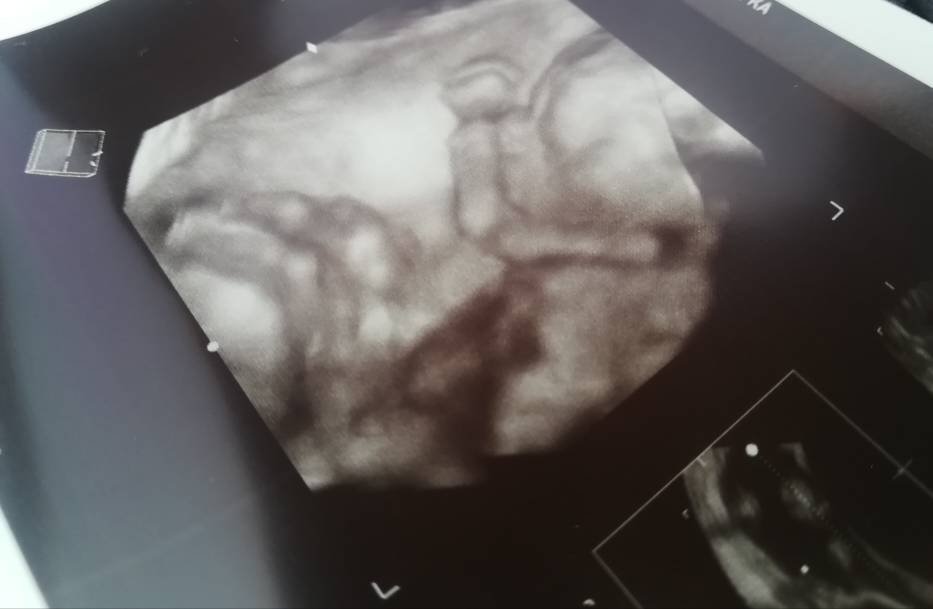

A Ty już masz pewność że w brzuszku ktoś rośnie:)

Jakieś objawy,odczucia?